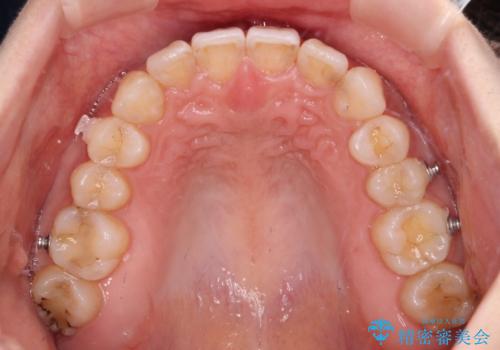

- 前歯のデコボコと深い咬み込みを気にして来院された患者様です。

インビザラインを用いて、前歯の叢生を解消するとともに、深い咬み合わせ(ディープバイト)を改善していくこととしました。

奥歯を後方に直立させることで深い咬み合わせを改善を図り、隠れていた下顎前歯が見えるほどになりました。